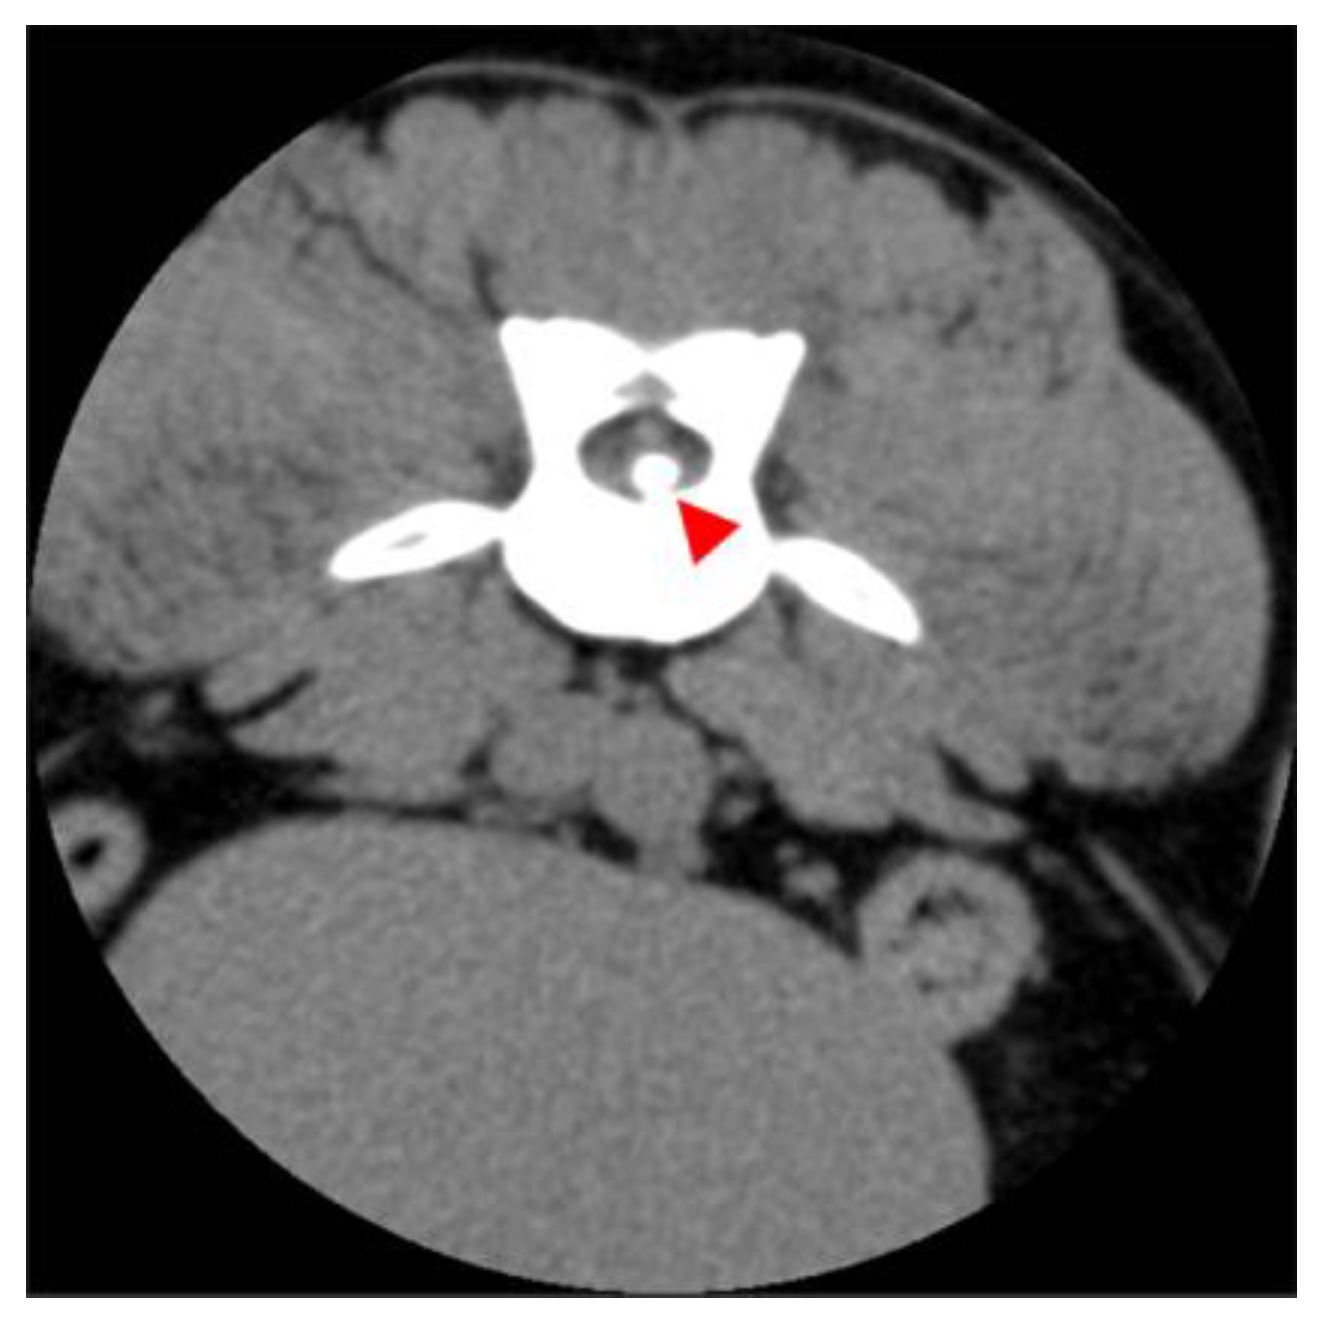

2.2. Diagnostic Imaging (CT and MRI)

2.3. Image Analysis